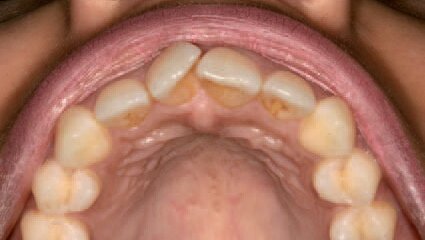

Slika 3. Okluzalni prikaz pre tretmana

Slika 4. Okluzalni prikaz nakon tretmana